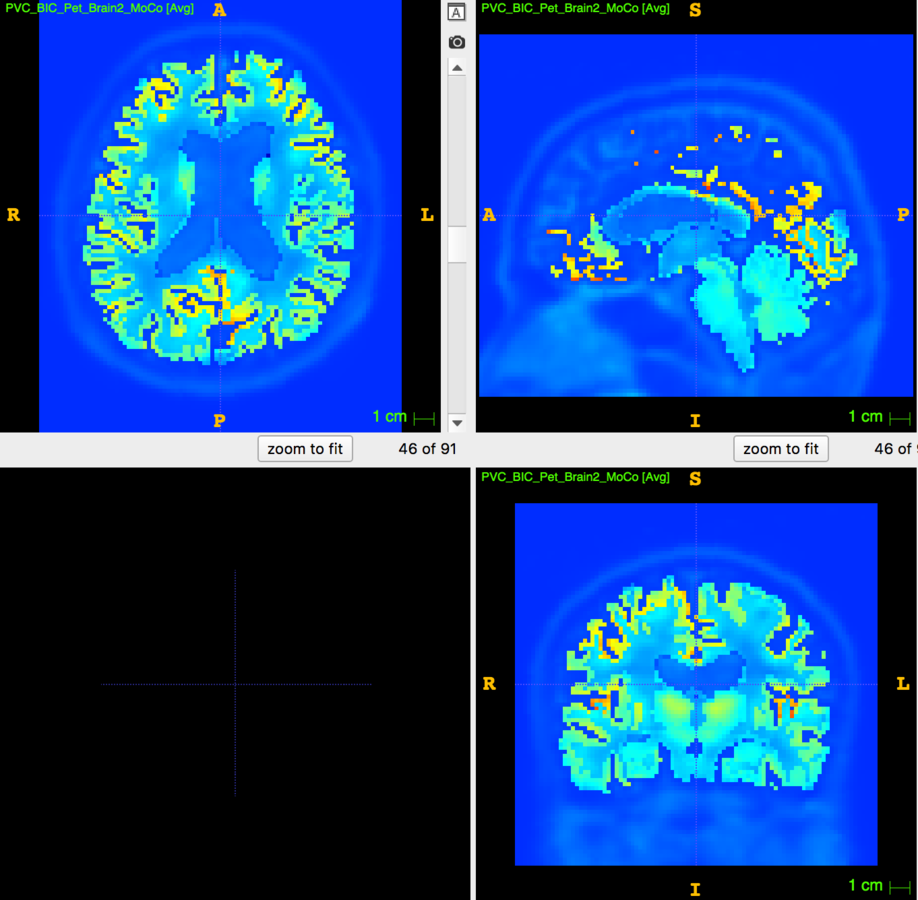

Partial Volume Correction

4. Glucose PET/MRI in MS

29 patients, 14 CIS/eRRMS and 15 RRMS underwent a PET/MRI with:

- MRI sequences: 3D T1, 3D FLAIR, 3D DIR

- 18Fdg PET in list-mode

The aim is to study the relationship between:

- Cortical Thickness

- WM/GM lesion number/volume

- aMRGlu

Results are hard to put together!

No correlation was demonstrated between CTh and WM and GM lesion load

No correlation was found between global and regional aMRglu and CTh.

aMRglu correlated with lesion load

Inverse correlation was found between:

- the total number of focal lesions (WM+GM lesions) and the global cortical aMRglu (R=-0.36 e p=0.04)

- WM lesion volume and number and cortical global aMRglu (R=-0.4 and p=0.02 for both)

-

GM lesion number with global aMRglu (R=-0.36, p=0.046)